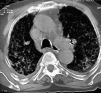

Fig. 3. Tomografía axial computarizada sin contraste intravenoso en el que se objetiva un patrón difuso intersticial reticulonodular. Condensación parenquimatosa en lóbulo medio del pulmón derecho con extensión bronquial y estenosis a ese nivel. Derrame pleural parietobasal bilateral.